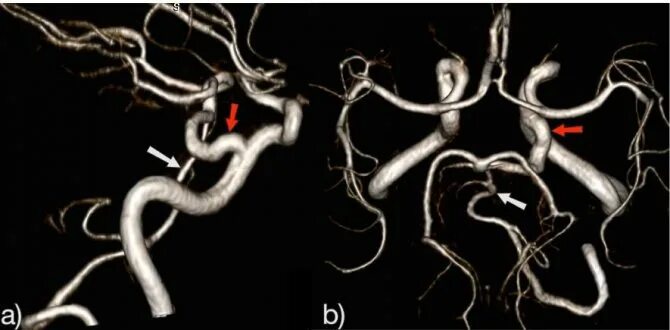

Гипоплазия интракраниального сегмента